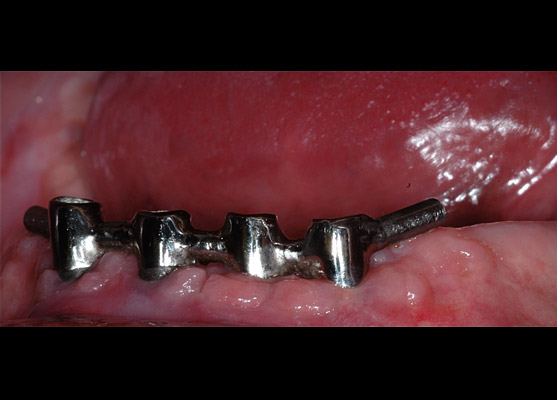

Chirurgie et implantologie

4 implants mandibulaires, barre et appareil complet